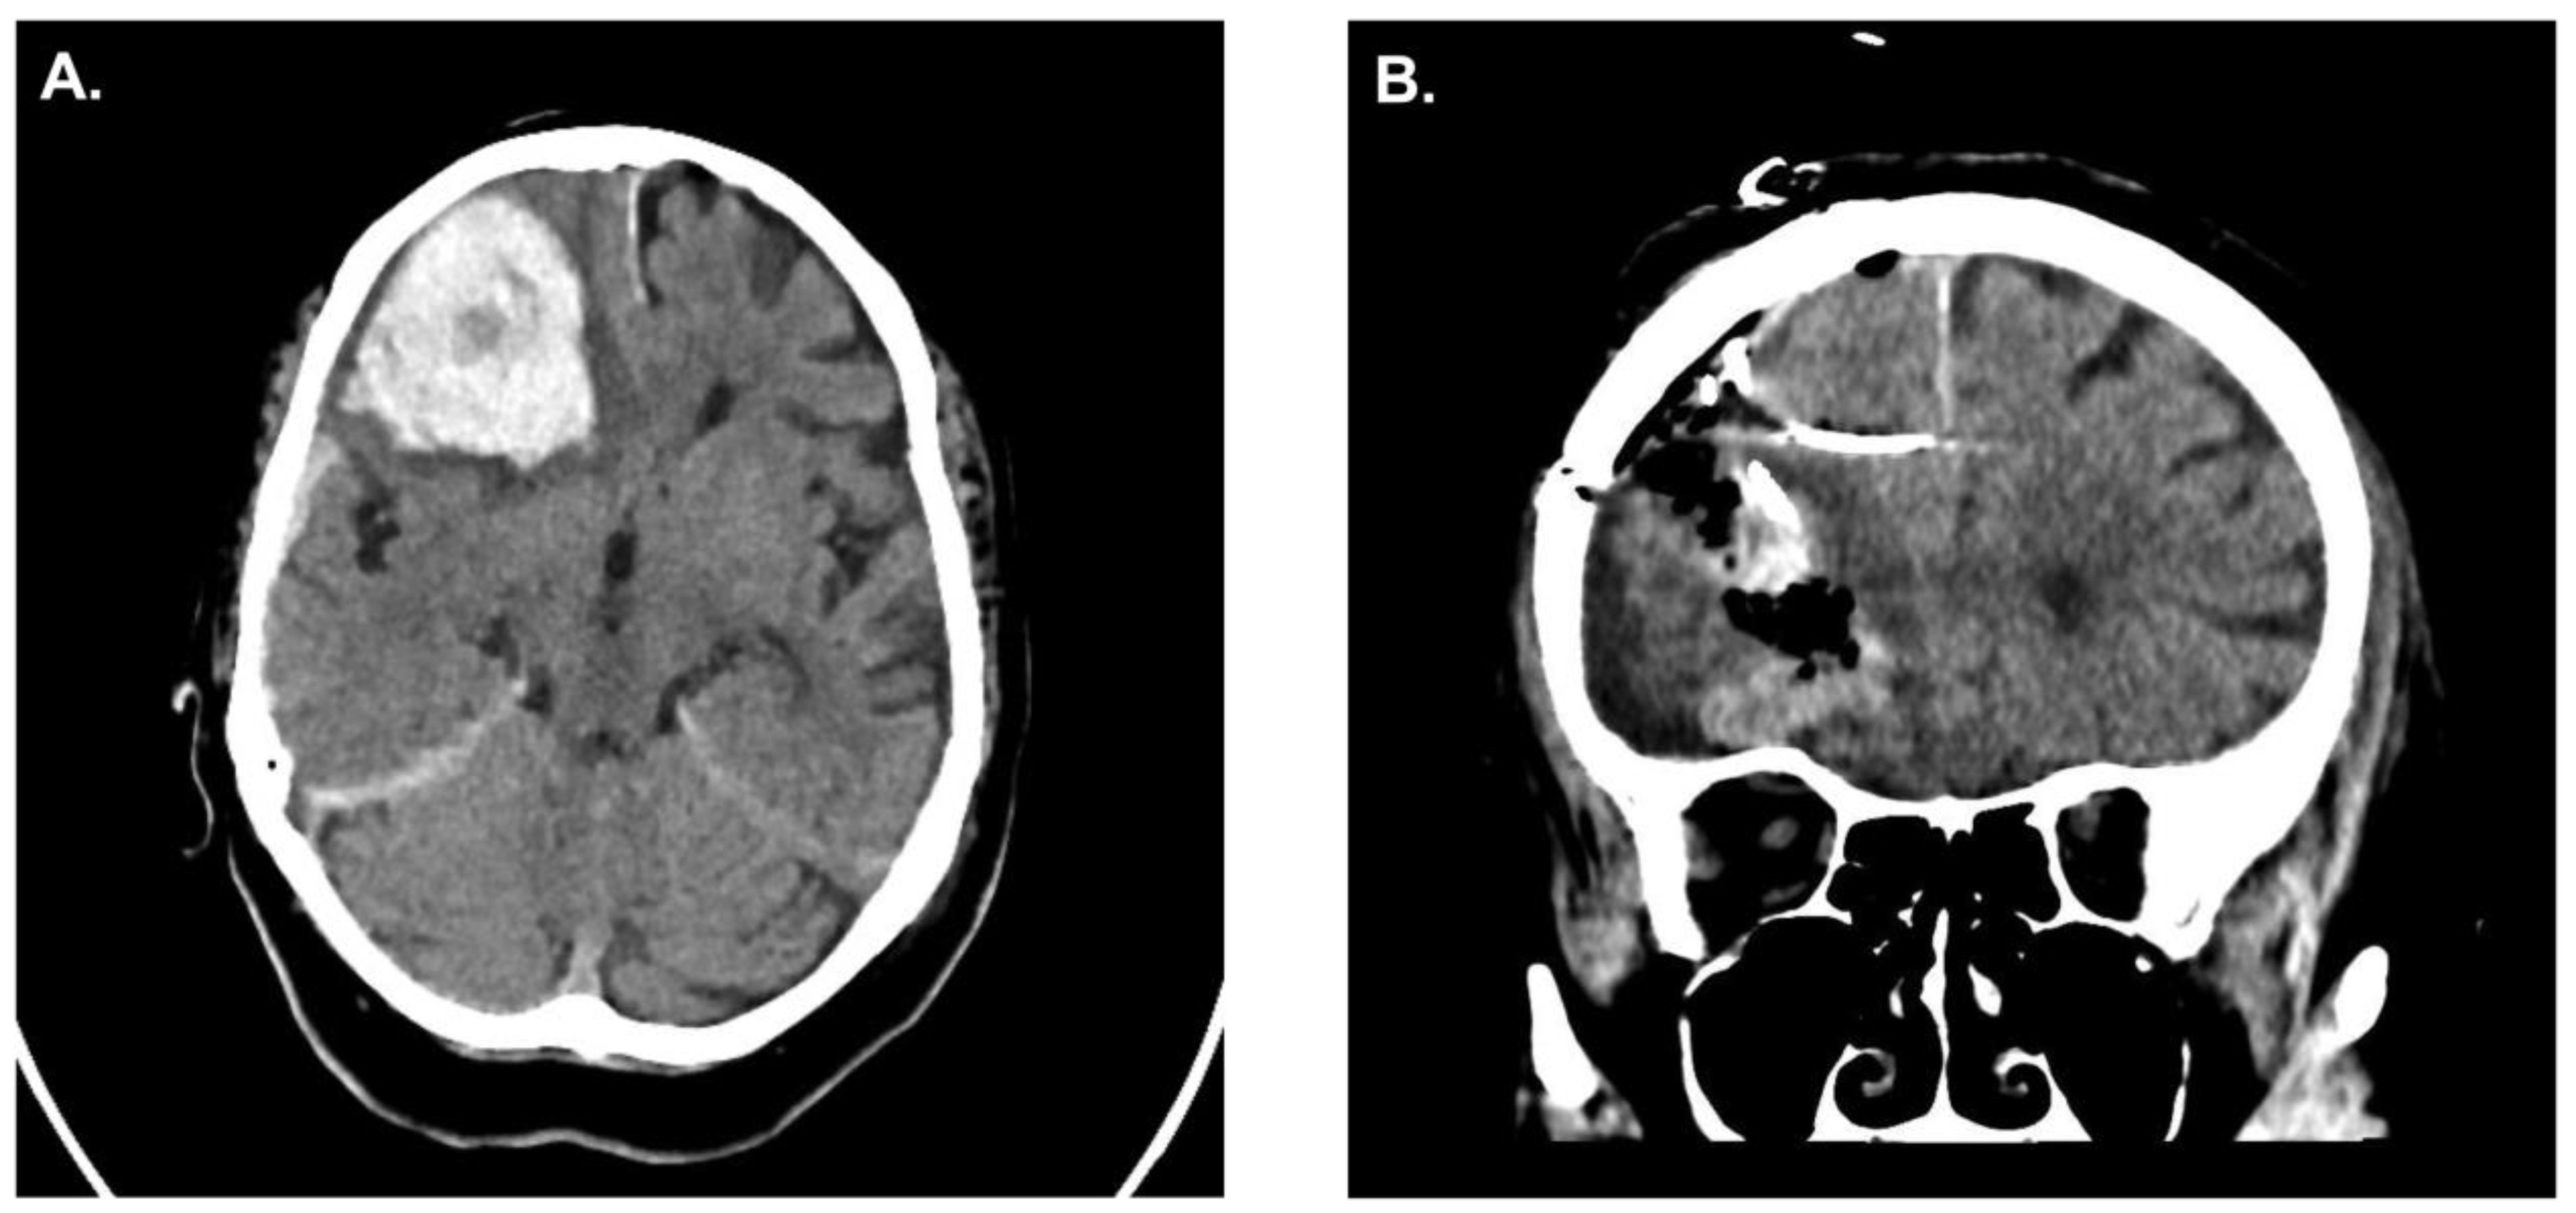

A 50-year-old patient was admitted to our hospital secondary to hypertensive intracerebral hemorrhage within the basal ganglia. After consent, the patient was taken to the operating room for surgical placement of two ICP monitoring devices. One probe air-pouch probe was placed within the hematoma cavity and the other one in the adjacent cerebral parenchyma. After surgery, the patient was transferred to the neuro-intensive care unit (ICU) for monitoring/care.

In the clinical pilot, similar results were observed in our patient that underwent simultaneous ICP measurement; the patient presented with a right frontal ICH and the indication for surgical evacuation was made (Figure 5A). After hematoma evacuation, ICP probes were inserted (Figure 5B). ICP probe located within the hematoma cavity consistently display higher ICPs values when compared to the ICP probe located in the adjacent parenchyma (Figure 6). No clinical or radiological signs of elevated ICP were observed during the course of observation in the neuro-ICU.

Figure 5. A. Preoperative CT scan of a patient with right frontal intracerebral hemorrhage. B. Postoperative CT scan showing hematoma evacuation with simultaneous ICP monitoring.